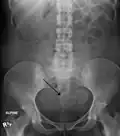

- A very large (9 cm) fibroid of the uterus which is causing pelvic congestion syndrome as seen on CT

- Two calcified fibroids (in the uterus)